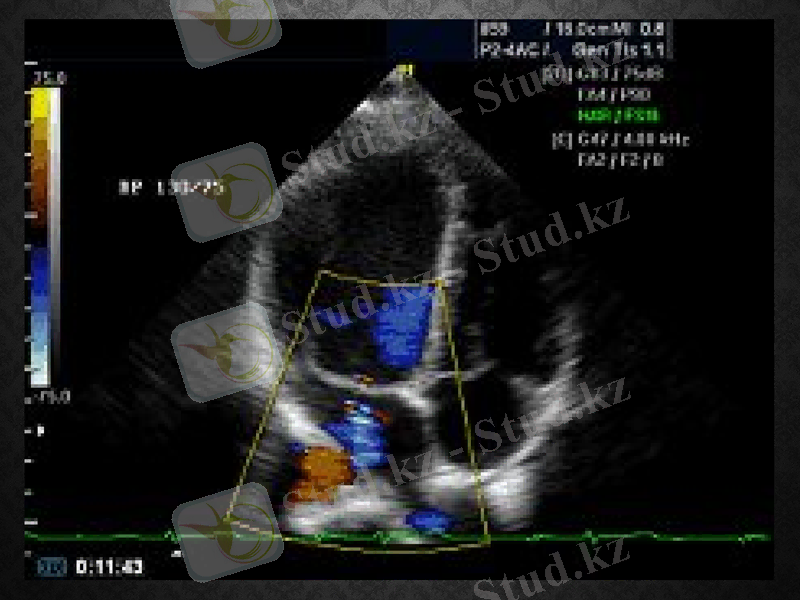

Эхокардиография - қазіргі заманғы жоғары информативті инвазивті емес ауырсынусыз және қауіпсіз жүрек қантамыр жүйесінің диагностикалау әдістерінің бірі болып табылады.

Эхокардиография беретін мүмкіншіліктер

1. Жүрек қуыстарының көлемдерін анықтауға 2. Жүрек клапандарының жағдайын және олардың қызметін бағалауға 3. Жүрек қабырғаларының қалыңдықтарын анықтауға 4. Жүрек қарыншаларының жиырылу мүмкіншіліктерін бағалауға

5. Жүректегі миокард инфарктінен кейінгі тыртықты өзгерістерді анықтауға

Эхокардиография өткізуге көрсеткіштер

Жүректің ишемиялық аурулары (ЖИА) ; Миокард инфарктісі (МИ) ; Артериальді гипертензия (АГ) ; Туа біткен және жүре пайда болған жүрек қантамыр ақаулары; Ревматизм; Жүрек өткізгіштігінің және ырғағының бұзылыстары; Жүректегі шуылдар; Жүректегі ісіктер Жүрекке операция жасағаннан кейінгі жағдайды бағалау

ЭхоКг түрлері

1. Доплер Эхокардиография 2. Өңеш арқылы Эхокардиография 3. Стресс - эхокардиография әдісі 4. Тамырішілік ультрадыбыс 5. Контрасты эхокардиография

Доплер Эхокардиография: Орталық гемодинамиканы бағалауға мүмкіндік беретін инвазивті емес әдіс. 1980 жылдан бері қолданылады. Доплер әдісімен зерттеу топографиялық анатомияны және жүрек гемодинамикасын бағалауға мүмкіндік береді. Өңеш арқылы Эхокардиография: Өңеш арқылы арнайы датчиктерді қолдану арқылы жүргізіледі. Бұл әдістің мүмкіншілігі өте жоғары. Арнайы трансдьюсер өңеш арқылы еңгізіліп, оның ортасында орналастырылады, сол жақ жүрекше маңайына. Бұл өте сапалы жүректің барлық құрылымдары туралы мәлімет алуға мүмкіндік береді. Өңештік трансдьюсер арқылы екі өлшемді кескін алуға және түсті доплер әдісін қолдануға да мүмкіндік береді. 180 градусқа бұруға мүмкіндік бар. Жүрек клапандарын ауыстыру және окклюзиялаушы аппараттармен хирургиялық араласулар кезінде қолданылады.